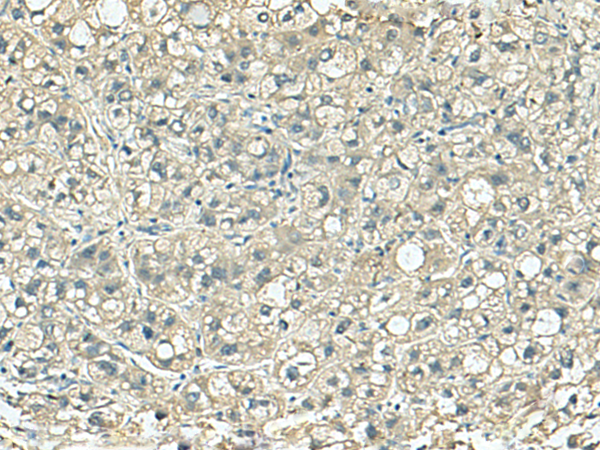

IHC positive control: |

Human liver cancer |

IHC Recommend dilution: |

150-300 |